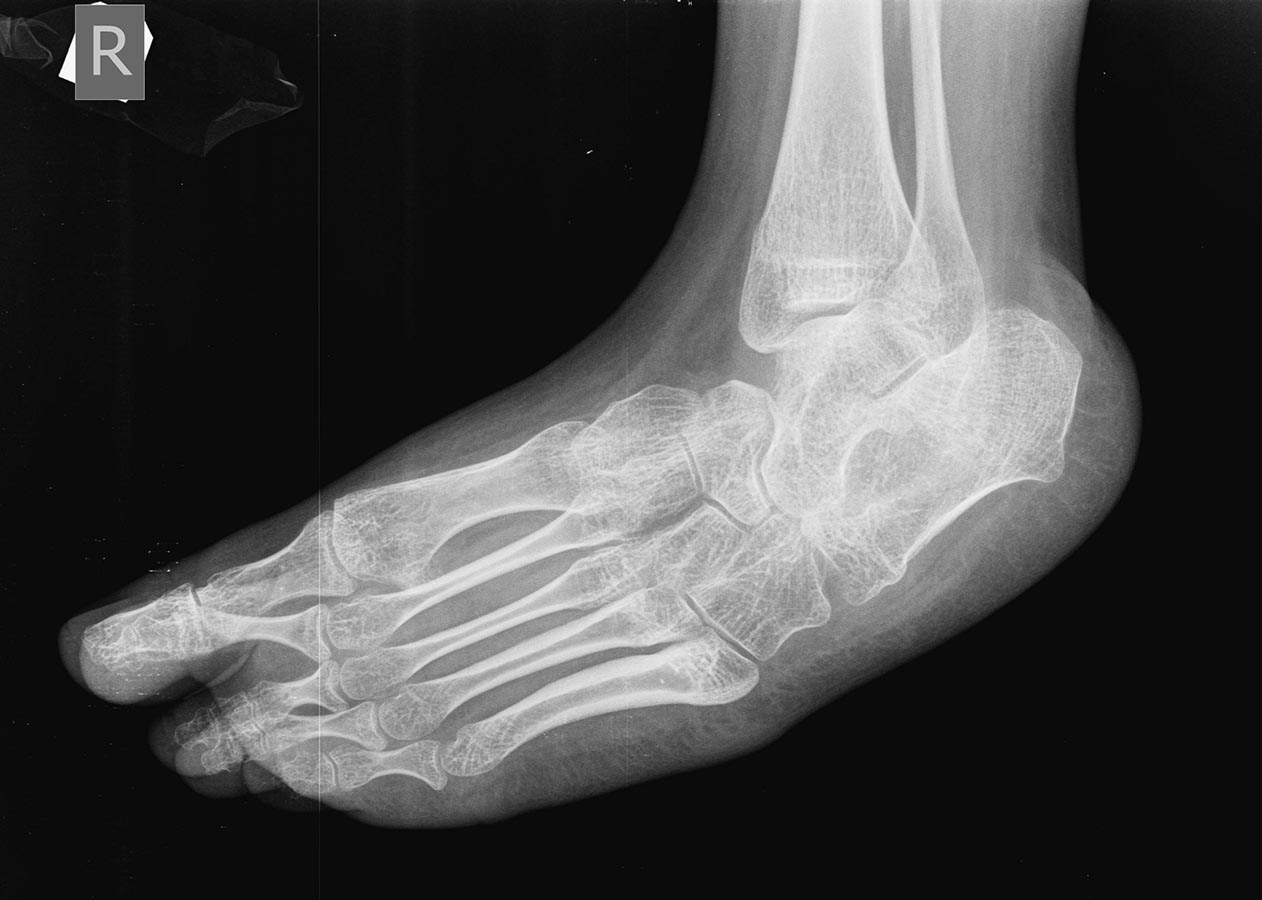

Девочка 15-и лет, страдает ДЦП

Уважаемый доктор Бахтамян, а что это за операция тенотомия икроножных мышц в подколенной ямке, наверное операция Страера имелось ввиду? "Хорошо разработана" и при этом девочка не ходит, а на фото тяжелая конская стопа. Так не бывает.

Откуда такая информация? Без рассечения дельтовидной связки не получить коррекцию варуса. Мягкотканного вмешательства достаточно не будет. На снимках выраженные нарушения формы костей стопы-и речи не идет о приемлемой биомеханике. Жуткая инконгруентность - хоть все сухожилия удлините, какой толк? Вызывает большие сомнения возможность почти полной пассивной коррекции деформации этих стоп. Но если она все-таки возможна - ничто не мешает выполнить ахиллопластику и трехсуставной артродез одномоментно без предварительного проведения гипсовой коррекции. Аппарат Илизарова для спастика - мучение для пациента и врача. Астрагалэктомия - зачем? Трехсуставной оставит голенстоп подвижным, после астрагалэктомии движений не будет. Да и просто не показана она здесь. Таранно-пяточный (подтаранный) сустав - не скакательный. Честно говоря, слышал только про скакательную связку стопы (пяточно-ладьевидная).

Снимок сделан в «произвольно-лежачем» положении, поэтому создаётся впечатление «грубой» деформации. В любом случае при патологии стопы при ДЦП функция важнее анатомии. Если Вы смогли вывести руками стопу до дорсифлексии, то на операционном столе вы выведите её ещё больше даже после Страйера. Варус тоже уйдёт (кстати, если Вы будете выводить стопу очень меденно, то, я думаю, варус ликвидируется даже при осмотре). У девочки диплегия и сгибательные контрактуры в коленных суставах, то есть, после удлиннения ахилловых сухожилий и капсулотомий большая вероятность развития crouch gait, это трагедия, которую трудно исправить. Лучше недокоррекция. В данном случае проблему нужно решать на уровне коленных и голеностопных суставов одномоментно. Разгибательные остеотомии н\3 бёдер + низведение надколенников + Страйер (эквинус не проблемма).

Леонид Сычевский 29 Апрель 2015, 00:22

Жалею, что поздно зашёл на этот топик. Вот смотрю я на фотографию - обычная,классическая стопа в эквиноварусной деформации при ДЦП. Смотрю Rg - снимки - обычные снимки эквиноварусной деформации при ДЦП, сделанные в том положении в котором они сделаны. Девочка ещё год назад ходила. Да это мечта любого ортопеда,занимающегося ДЦП. Какие артродезы и капсулотомии с пересадками. Поверьте мне Доктор Бахтамян, дадите наркоз, стопы выведутся, проверите Silverscold на операционном столе и , в зависимости от результата - удлиннение ахилла или Страйер. Я бы делал пересадку Ахилла кпереди и то что я написал выше, но это наши заморочки. Вам я рекомендую Страйера при сгибательных контрактурах в коленных суставах (лучше лёгкий эквинус чем crouch gait, тем более, что девочка уже выросла и рецидивов на будет). Операция 10 минут и Вы будете героем. Таких пациентов я прооперировал сотни. самая благодарная операция при ДЦП.

Уважаемый доктор Бхатамян, не делайте Rg-снимки стоп больным с ДЦП. Они не несут информации, не играют роль в принятии решения и вводят в заблуждение окружающих. Когда следующий раз придёт к Вам эта больная положите её на живот согните одну из ног в коленном суставе, положите свои ладони ей на стопы и медленно, очень медленно выведите стопы. Это, для Вас, будет доказательством того, что никаких «грубо-фиксированно-инконгруэтных» деформаций нет. Конечно, лечить больных с ДЦП не видя их трудно и глупо. Но, к счастью для нас, клинико-двигательные нарушения у больных с симметричной формой спастической диплегии проходят по определённому сценарию. У этой девочки 3 патерн этих нарушений (судя по фотографии и Вашим описаниям). Эквиноварусная деформация-сгибательная контрактура коленных суставов-сгибательная контрактура тазобедренных суставов (хотя Вы об этом не пишете, но она есть). Изолированное удлинение ахилловых сухожилий, тем более с капсулотомиями и прочее ПРОТИВОПОКАЗАНО. Исход - crouch gait. Это беда. Если дополнить релизом хамстрингов, исход передняя тазовая инклинация - это полбеды.Нужно делать релиз хамстрингов и релиз илиопсоас из внутритазового доступа (это принципиально). Но в 15-летнем возрасте релиз хамстрингов может не вывести коленные суставы до коррекции, поэтому я писал об остеотомиях. Если у Вас нет опыта лечения этих больных, то лучше не заморачиваться на всём этом, а сделать рецессиию гастрокнемиус (Страйер, Вульпеус, Бейкер, что лучше получается) и всё. Девочка опять будет ходить. Хотя плохо. Чтобы хорошо, запишите видео и вышлите, можно в личку. Я распишу операции. Ну,... моё мнение. Да, сделайте снимки тазобедренных суставов.